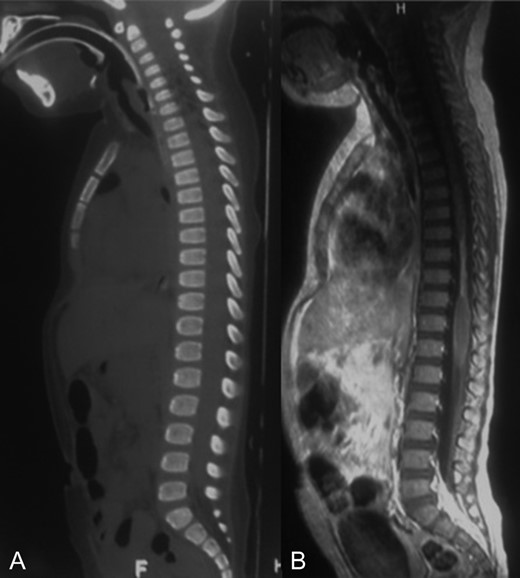

A 2-year-old female patient was referred to our institution after suffering a motor-vehicle accident. She was admitted under sedation with miotic pupils, left iliac hematoma and cervical collar. At admission, brain, chest, abdominal and pelvic CT scans reported right pneumothorax and a hyperdense hepatic lesion. Spine CT scan showed no fracture or any other pathologic findings (Fig. 1A).

A-B: A. Sagittal bone window of spine showing normal alignment and no fracture. B. Sagittal T1 contrast enhanced sequence showing a narrowed spinal cord from T7 to T10 that could correspond to gliosis and edema.

MRI showed a narrowing lesion of the spinal cord from T7 to T10 (Figs 1B, 2A and B).